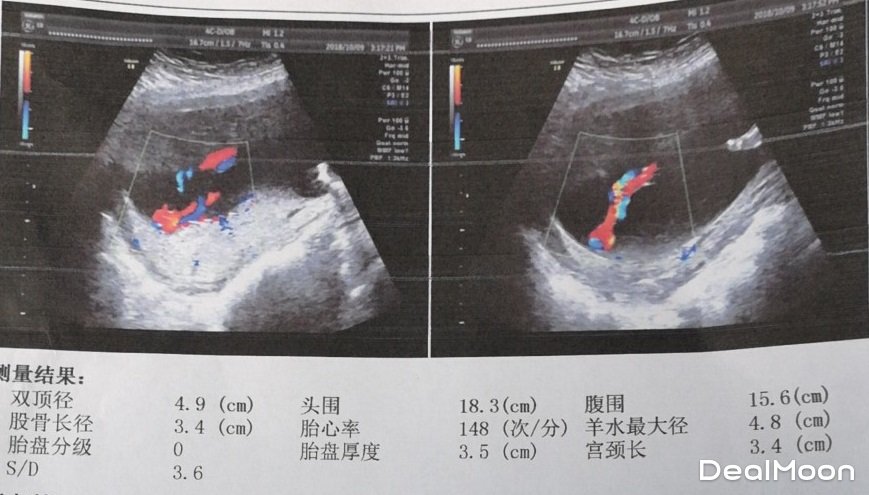

本周最重要的产检就是大排畸啦,准妈可以选择三维或者四维来排畸,清晰了解胎宝宝组织器官发育的情况,如心脏病、唇裂、泌尿系统畸形等。在b超单上,也会出现很多数据,下面就一起来看看这些数据代表啥吧~

BPD双顶径:是胎宝宝头部左右两侧之间最宽部位的长度。孕中期以后,在推算胎宝宝体重时,也需要测量BPD,孕5月后,双顶径基本与怀孕月份相符合。比如孕7月,BPD为7cm,孕8月为8cm。

HC头围:是测量胎宝宝头的一周的长度数值,用于确认胎宝宝的发育状态。

AC腹围:腹部周长,测量的是胎儿腹部一周的长度

S/D指数:是胎宝宝脐动脉收缩压与舒张压的比值,正常情况下,随着孕周增加,S下降,D升高,比值下降。

FL股骨长:大腿骨的长轴,用于推断孕中、晚期的妊娠周数。

LV侧脑室:正常应该在1cm以下,1~1.5cm算轻度危险,1.5cm以上就有点危险了。